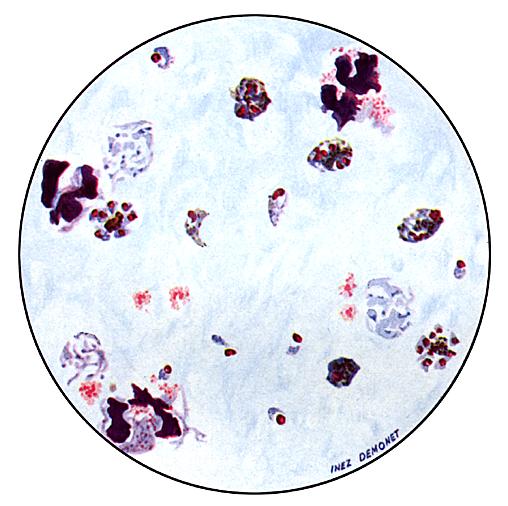

Plasmodium malariae: Blood Stage Parasites

Thin Blood Smears

Fig. 1: Normal red cell; Figs. 2-5: Young trophozoites (rings); Figs. 6-13: Trophozoites; Figs. 14-22: Schizonts; Fig. 23: Developing gametocyte; Fig. 24: Macrogametocyte (female); Fig. 25:  Microgametocyte (male).

Illustration from: Coatney GR, Collins WE, Warren M, Contacos PG. The Primate Malarias. Bethesda: U.S. Department of Health, Education and Welfare; 1971.